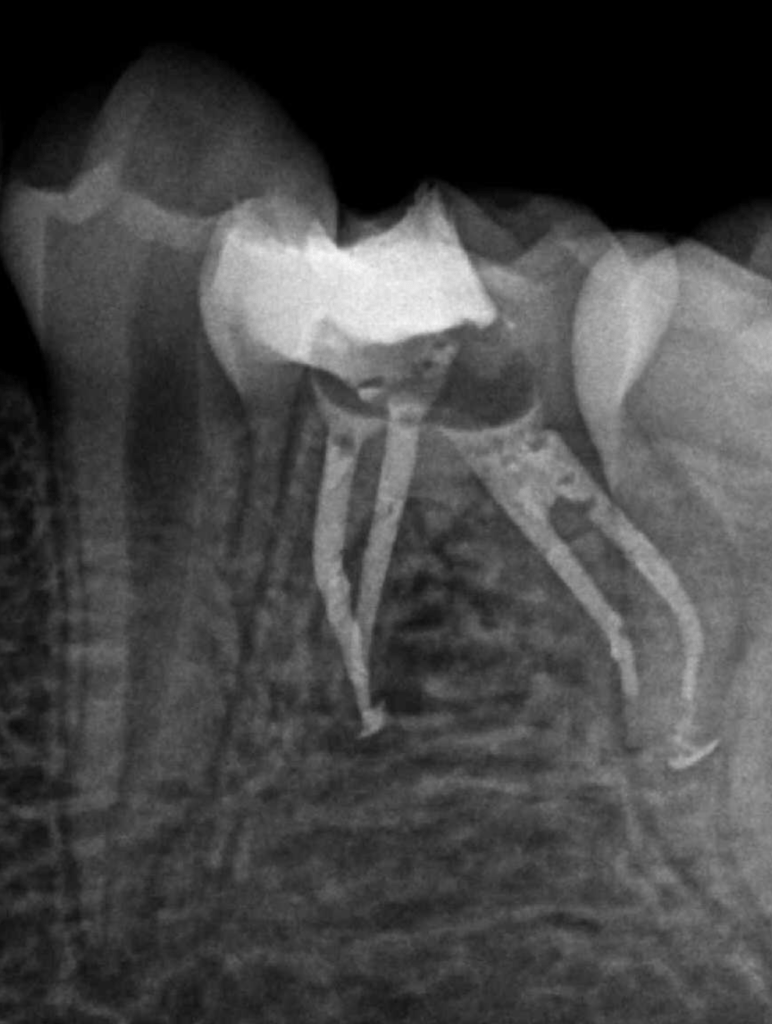

Reco preendo, 2o Molar superior